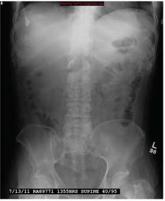

A 54-year-old man presents with a complaint of a two-week history of severe low back pain. He denies any injury or trauma. The pain is so severe that ...